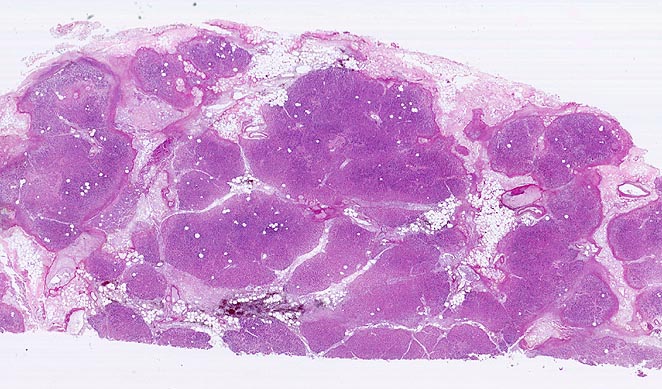

Das Spektrum reicht von Ödem und Infiltraten neutrophiler Granulozyten ohne oder mit kleinen Fettgewebsnekrosen bei der interstitiell-ödematösen Variante über großflächige hämorrhagische Nekrosen im peripankreatischen Fettgewebe und im Pankreasparenchym bei der nekrotisch-hämorrhagischen Variante (Kurspräparat). Das peripankreatische Fettgewebe wird bei der nekrotisch-hämorrhagischen Variante durchsetzt von grösseren Fettgewebsnekrosen mit Verseifung, die gesäumt werden von dichten Infiltraten neutrophiler Granulozyten teils mit Abszessbildung. Die Hämorrhagien kommen durch Wandnekrosen kleiner und mittelgrosser Venen im peripankreatischen Fettgewebe zustande.

• Unregelmässige Nekrosestrassen durchziehen Fettgewebe und Pankreasparenchym.

• Die Grenzen zwischen vitalem und nekrotischem Gewebe sind unscharf.

• Frische, teils hämorrhagische autodigestive Kolliquationsnekrosen von Pankreasparenchym und Fettgewebe demarkiert von zerfallenden neutrophilen Granulozyten.

• Innerhalb der Nekroseareale Ablagerungen von amorphem gelborangem Hämatoidin (eisenfreies extrazelluläres Hämoglobinabbauprodukt).

• Nachweis kokkoider und fadenförmiger Bakterien im nekrotischen Fettgewebe. Das sollte der Kliniker dem Pathologen mitteilen: